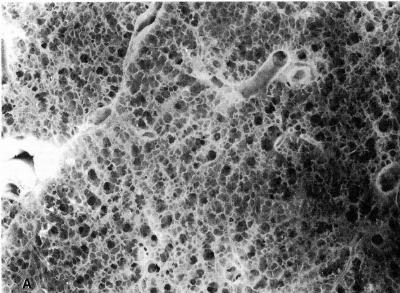

Emphysema, most often brought on by smoking, affects an estimated 60 million people worldwide with more than 3 million sufferers in the United States. There is no cure. It's a chronic, progressive, and irreversible lung disease characterized by the destruction of lung tissue. The loss of the lungs' natural elasticity and the collapse of airways in the lung combine so that the lungs can no longer deflate to let air in. The patient is in a permanent state of "breathlessness" – sucking in rapid, shallow breaths. Even the most nominal physical activities become difficult for emphysema patients and many become dependent on oxygen therapy.

Sterman adds, "Given that emphysema is such a devastating disease associated with permanent destruction of the small air sacs (alveoli) which allow the lungs to function -- any new potential intervention could offer substantial relief to the millions of sufferers in this country."